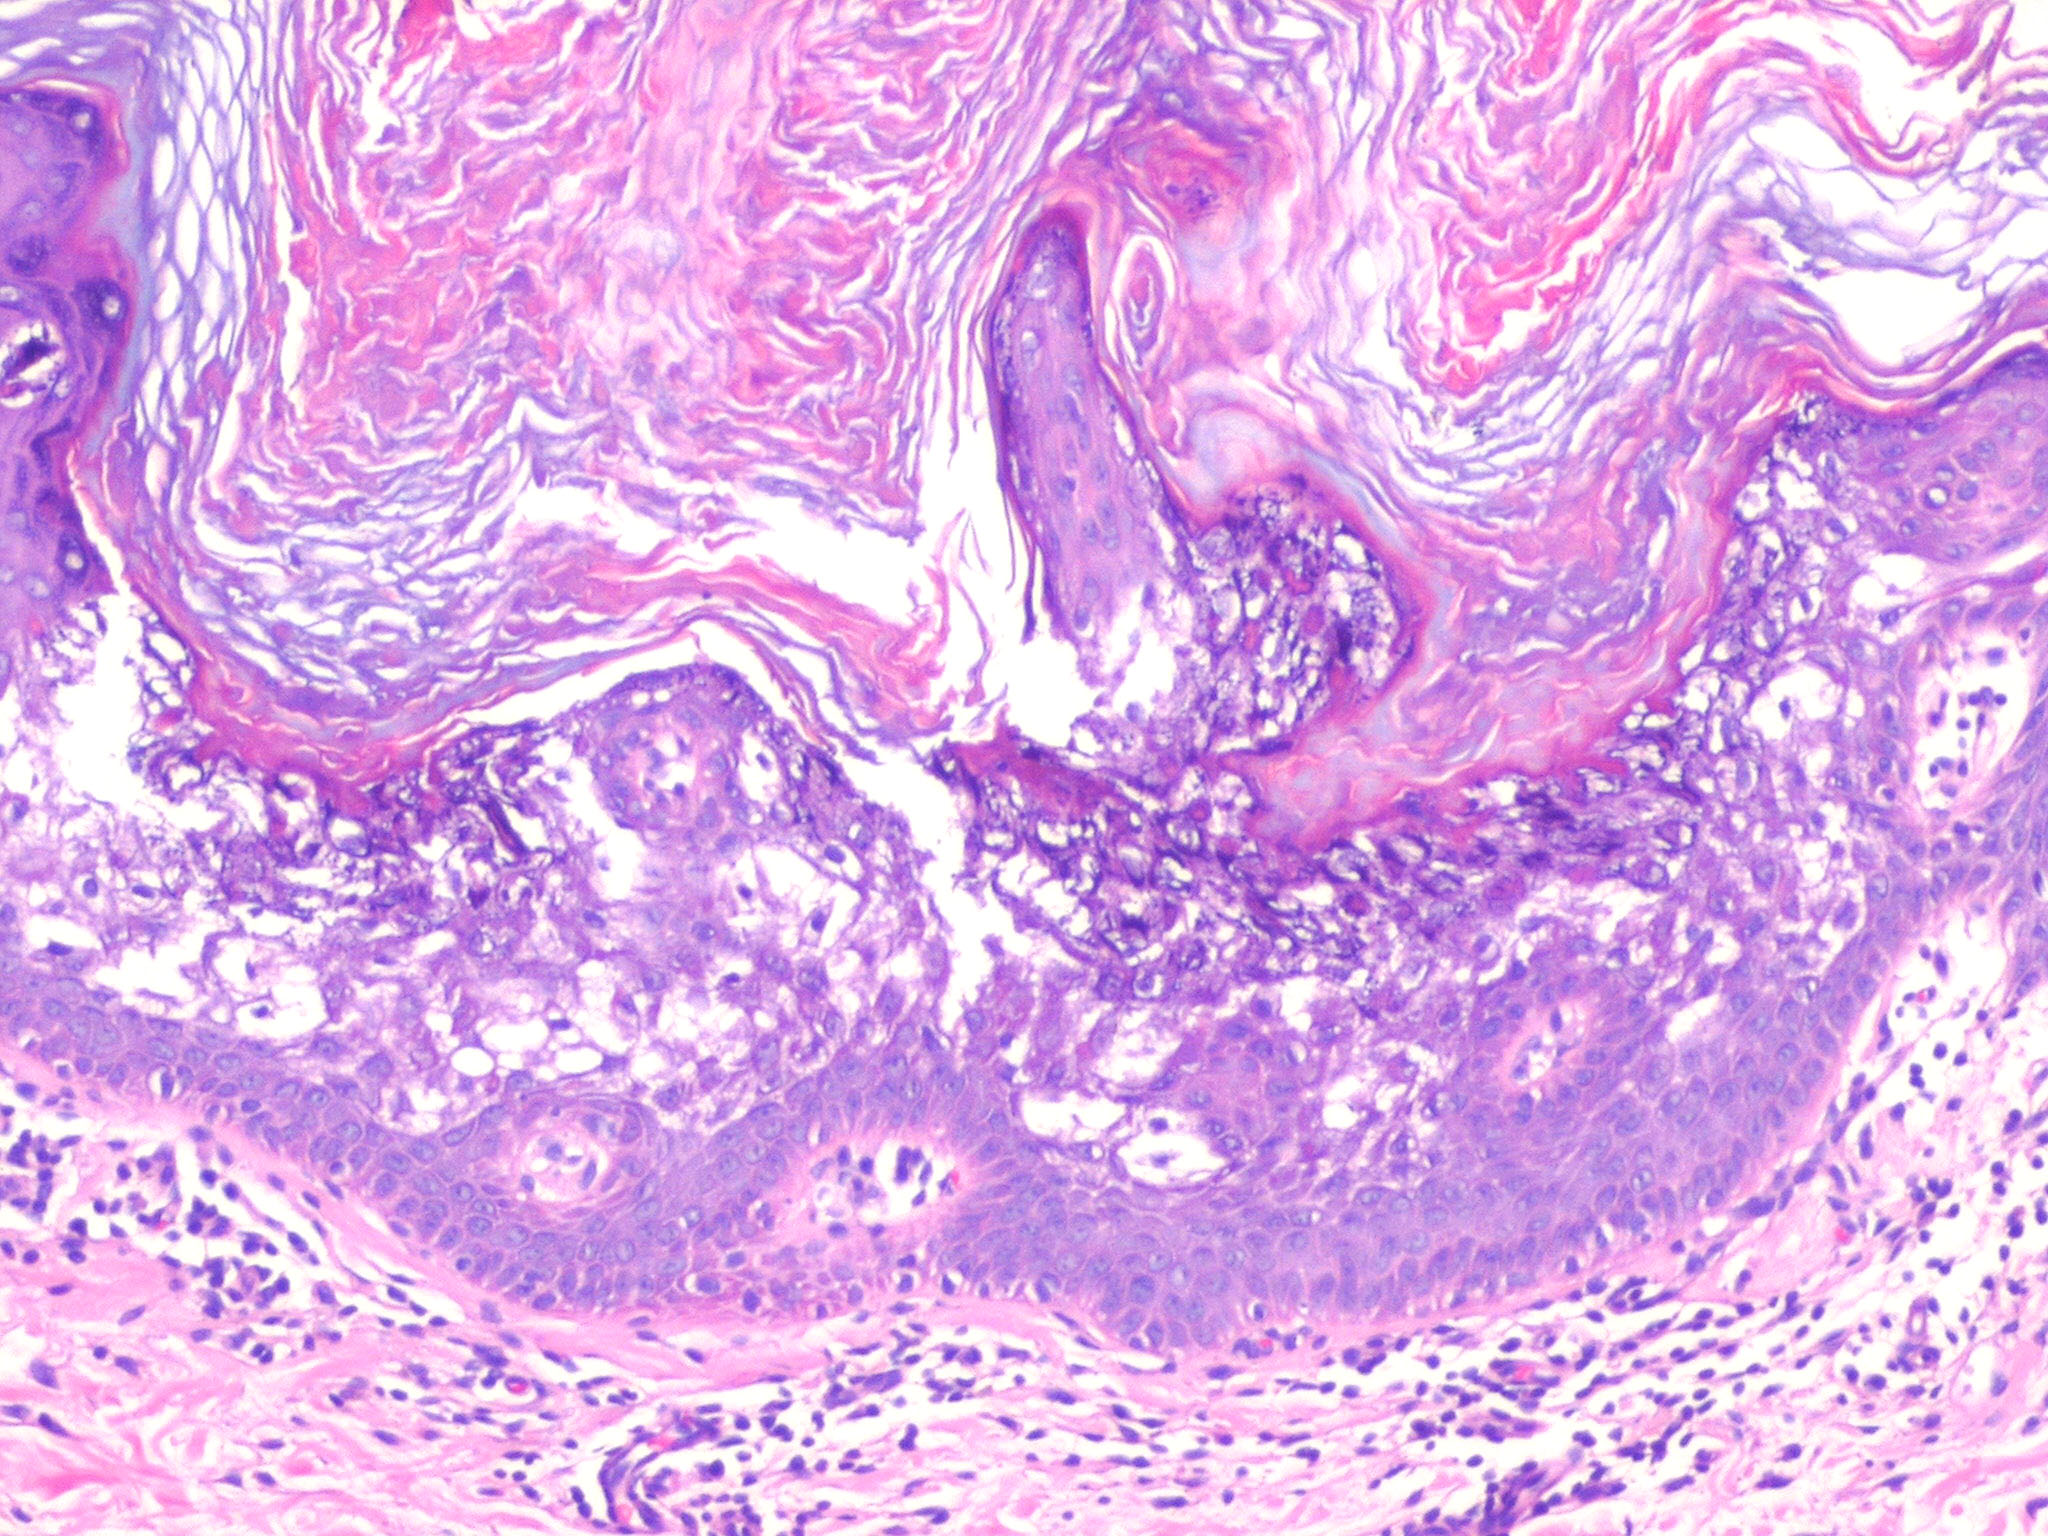

Histopathology. A characteristic histologic picture is seen in the epidermis and is referred to either as epidermolytic hyperkeratosis or as granular degeneration . It is present in bullous as well as in non bullous areas. There are variously sized clear spaces around the nuclei in the upper stratum spinosum and in the stratum granulosum. Peripheral to the clear spaces, the cells show indistinct boundaries formed by lightly staining material or by keratohyaline granules. A markedly thickened granular layer containing an increased number of irregularly shaped keratohyaline granules and compact hyperkeratosis is observed (14). When bullae form, they arise intraepidermally through separation of edematous cells from one another . The upper dermis shows a moderately severe, chronic inflammatory infiltrate. Mitotic figures are five times more numerous than in normal epidermis . Pathogenesis. Defects in keratin genes (KRT1 and KRT10) (16) are now known to be associated with this disorder. Mutations have been found in the carboxy terminal of the rod domain of keratin 1 and the aminoterminal of the rod domain of keratin 10 (17). The essential electron microscopic features are excessive production of tonofilaments and excessive and premature formation of keratohyaline granules; thus, at the periphery of the cells, numerous keratohyaline granules are embedded in thick shells of irregularly clumped tonofilaments (. The desmosomes appear normal, but the association of tonofilaments and desmosomes is disturbed, so many desmosomes are attached to only one keratinocyte instead of connecting two neighboring keratinocytes. Because of this disturbance in desmosomal attachment, blister formation takes place and real acantholysis occurs . Labeling with tritiated thymidine reveals greatly increased proliferative activity in the epidermis . It can be concluded that keratinization is both excessive and abnormal. Differential Diagnosis. Although the histologic picture of epidermolytic hyperkeratosis is diagnostic for the type of ichthyosis called epidermolytic hyperkeratosis, it is not specific for it. Hyperkeratosis is found also in several other seemingly unrelated conditions : epidermolytic keratosis palmaris et plantaris, solitary epidermolytic acanthoma, disseminated epidermolytic acanthoma, and linear epidermal nevus, usually of the systematized type. This latter entity was thought to be an entirely different condition than epidermolytic hyperkeratosis but with similar histologic findings. However, it is now known that epidermal nevi of the epidermolytic hyperkeratotic type are a mosaic genetic disorder of suprabasal keratin (l.e., point mutations of 10k alleles of epidermal cells in keratinocytes from lesional skin) that can be transmitted to offspring producing generalized epidermolytic hyperkeratosis . Epidermolytic hyperkeratosis can be an incidental finding in a variety of conditions